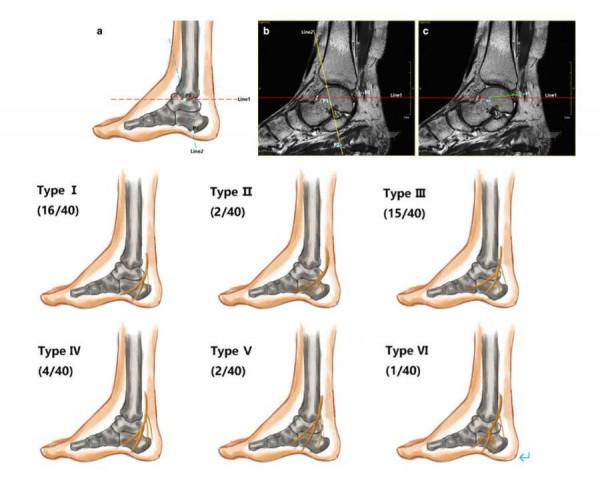

中心醫學影像科張彥醫師採用磁共振3D序列重建的方法,實現了對跟骨內側神經及跟骨下神經這些相對終末細小周圍神經的形態學顯示,追蹤了其走行及分佈區域,並進行了詳細的分型,這是國內首次對踝關節處脛神經的細小分支磁共振形態學方面進行的研究,此研究將極大地促進周圍神經相關的周圍神經影像學及臨床應用工作,也對周圍神經病變的評估提供了新的方法。相關研究論文《An MRI study of the tibial nerve in the ankle canal and its branches: a method of multiplanar reformation with 3D-FIESTA-C sequences》於2021年3月份發表在施普林格旗下的BMC Medical Imaging雜誌上。